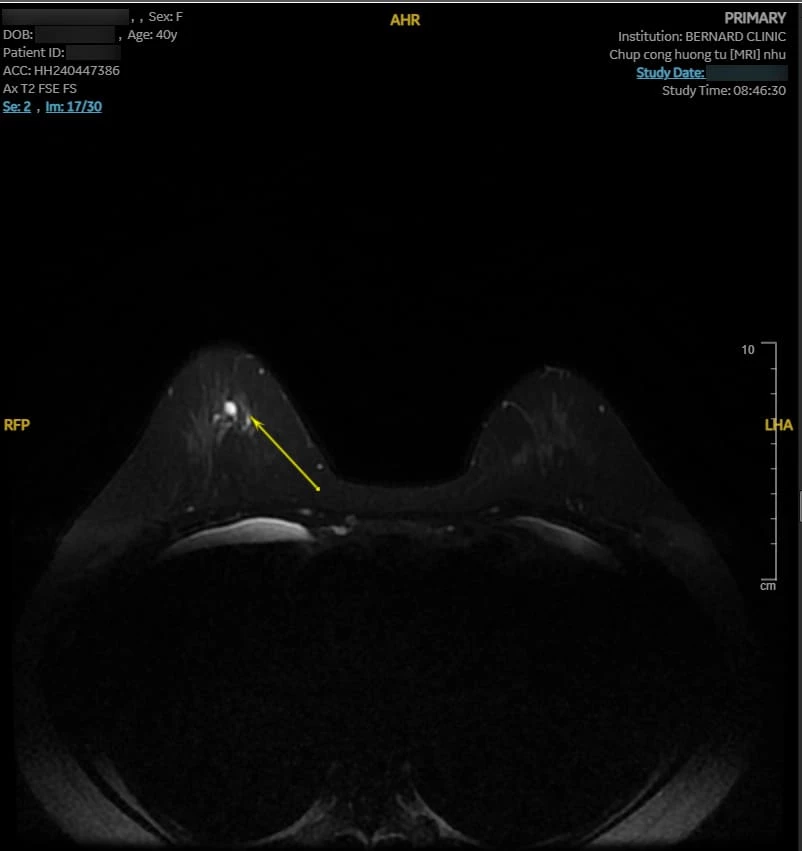

Hình ảnh MRI cho thấy nhiều bất thường. Vú phải có nang vú vị trí 6 giờ, cách núm vú 3cm, d-7mm, phân loại BI-RADS 2. Vú trái có bất thường tín hiệu diện rộng 1/2 dưới (6 - 8 giờ), giới hạn bờ kém rõ, tổn thương dạng đám/nốt/đường, BI-RADS 4.

| Hình ảnh tổn thương qua MRI với Coil Nhũ chuyên biệt, chụp tại Bernard Healthcare |